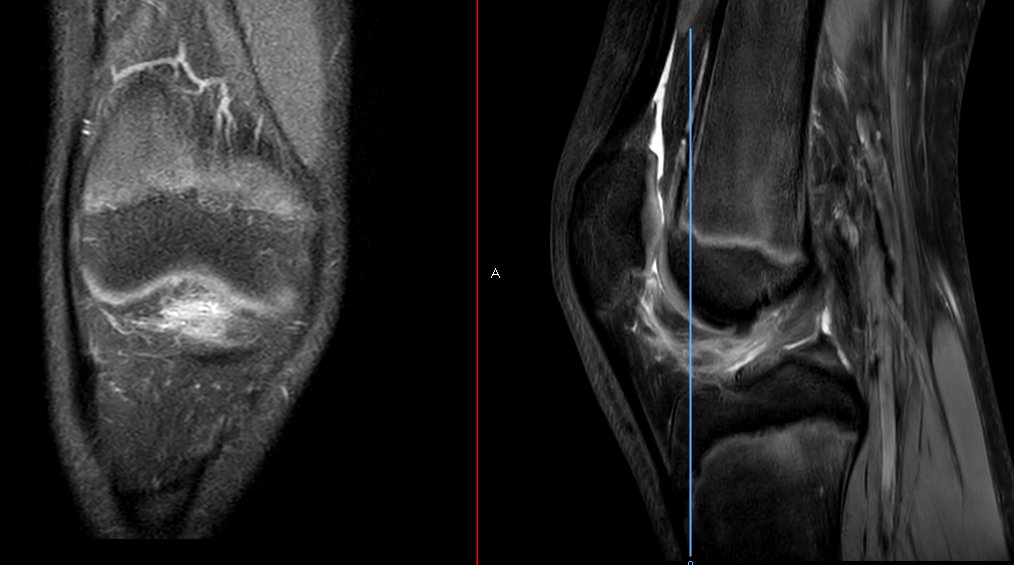

WB-DW MRI or FDG PET/CT for myeloma response? This review breaks down strengths, pitfalls, and standardized criteria (MY-RADS & Deauville). Learn how to integrate both for accurate posttreatment assessment and improved confidence. bit.ly/4viX1Wi